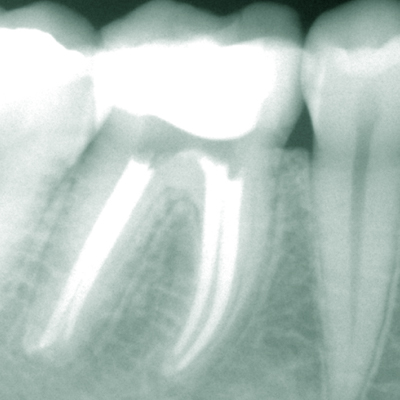

Endodontie (Wurzelbehandlungen)

Professionell durchgeführte exakte Wurzelbehandlungen ermöglichen die Rettung eigener Zähne bei Entzündung oder nach Absterben des Gefäß-Nervengewebes (Pulpa) im Inneren des Zahnes in den meisten Fällen.Keine Angst, die Behandlung ist praktisch immer schmerzfrei. Wir verwenden sowohl für die Wurzelbehandlung als auch für Wurzelspitzenresektionen (Operation an der Wurzelspitze) modernste Techniken und neueste technische Hilfsmittel wie z.B. ein Operationsmikroskop oder ein Piezo-Ultraschallgerät. Somit können wir auch schwierige Fälle, wie Entfernen von Stiftaufbauten oder frakturierten Instrumenten, Wurzelkanalrevisionen oder komplizierte endodontisch-chirurgische Fälle lösen.